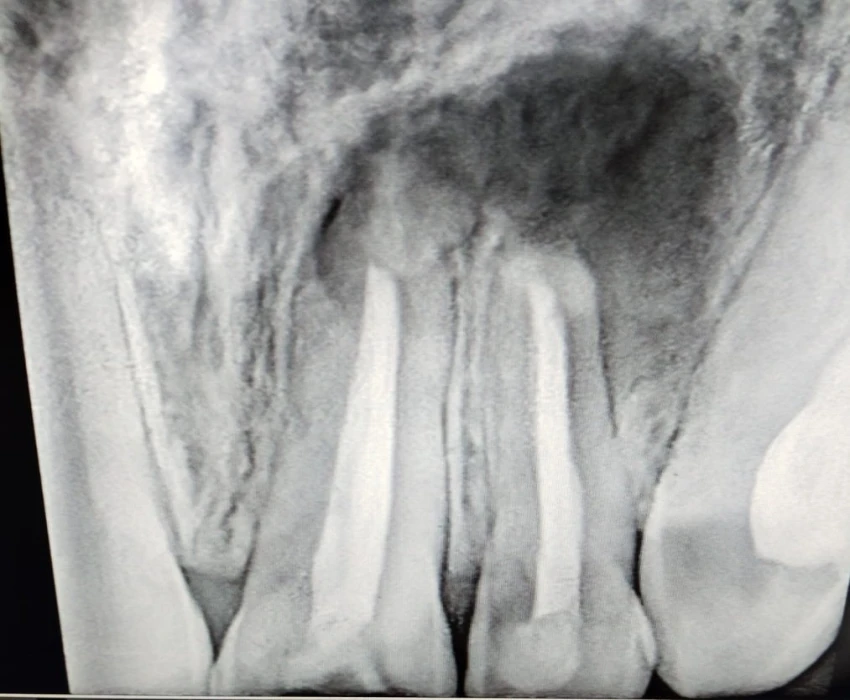

Diagnosis: Periapical abscess wrt 21,22

Treatment plan: RCT wrt 21 and 22 followed by periapical surgery.

The endodontic treatment was initiated wrt 21 & 22, working length determined and BMP completed. The presence of sinus opening and lack of any discharge from the canals, implored the need for calcium hydroxide dressing, following which, the sinus opening resolved and obturation was done. Apicoectomy was performed wrt 21&22, retrograde cavity was restored with biodentine and the lesion was curretted and packed with PRF to promote better healing. The patient was asymptomatic at his 7-day follow up and exhibited uneventful healing.